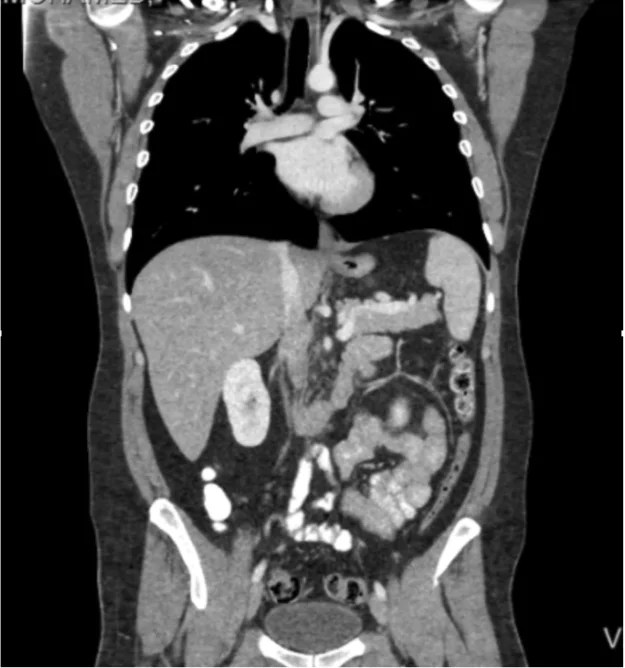

| 복부 CT | 10 | 약 3년치 자연 방사선량 |

위 표에서 보듯, 일반적인 X-ray는 우리가 매일 접하는 자연 방사선과 큰 차이가 없습니다. 다만 CT 촬영은 상대적으로 높은 방사선량을 사용하기 때문에 불안해하는 경우가 많습니다. 그러나 필요한 경우 CT는 생명을 구하는 중요한 도구입니다.

예: 복부 CT 촬영 한 번으로 조기 암을 발견할 수 있다면, 방사선으로 인한 위험보다 의학적 이득이 훨씬 큽니다.

제가 응급실에서 근무하면서 가장 기억에 남는 사례 중 하나는, 40대 환자분이 단순 복부 통증으로 CT를 찍은 경우였습니다. 결과적으로 초기 단계의 대장암이 발견되어 빠르게 수술과 치료를 받을 수 있었죠. 만약 방사선이 두려워 검사를 미루셨다면, 치료 시기를 놓쳤을 수도 있었습니다. 이처럼 진단 방사선은 ‘위험’보다 ‘생명을 구하는 기회’가 더 크다는 점을 꼭 강조드리고 싶습니다.